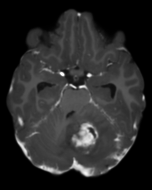

Refer to captionRefer to caption𝐱PCsubscript𝐱PC\mathbf{x}_{\mathrm{PC}}bold_x start_POSTSUBSCRIPT roman_PC end_POSTSUBSCRIPTRefer to captionRefer to caption𝐱LDsubscript𝐱LD\mathbf{x}_{\mathrm{LD}}bold_x start_POSTSUBSCRIPT roman_LD end_POSTSUBSCRIPTRefer to captionRefer to caption𝐱SDsubscript𝐱SD\mathbf{x}_{\mathrm{SD}}bold_x start_POSTSUBSCRIPT roman_SD end_POSTSUBSCRIPTRefer to captionRefer to captionAm-3D [14]Refer to captionRefer to captionPa-2.5D [8]Refer to captionRefer to caption𝐱~SDsubscript~𝐱SD\tilde{\mathbf{x}}_{\mathrm{SD}}over~ start_ARG bold_x end_ARG start_POSTSUBSCRIPT roman_SD end_POSTSUBSCRIPT (ours)ptPhilips Achieva 3TGadobutrol dLD=0.10subscript𝑑LD0.10d_{\mathrm{LD}}=0.10italic_d start_POSTSUBSCRIPT roman_LD end_POSTSUBSCRIPT = 0.10ptPhilips Ingenia 1.5TGadoterate dLD=0.33subscript𝑑LD0.33d_{\mathrm{LD}}=0.33italic_d start_POSTSUBSCRIPT roman_LD end_POSTSUBSCRIPT = 0.33Refer to captionRefer to caption𝐱PCsubscript𝐱PC\mathbf{x}_{\mathrm{PC}}bold_x start_POSTSUBSCRIPT roman_PC end_POSTSUBSCRIPTRefer to captionRefer to caption𝐱LDsubscript𝐱LD\mathbf{x}_{\mathrm{LD}}bold_x start_POSTSUBSCRIPT roman_LD end_POSTSUBSCRIPTRefer to captionRefer to caption𝐱SDsubscript𝐱SD\mathbf{x}_{\mathrm{SD}}bold_x start_POSTSUBSCRIPT roman_SD end_POSTSUBSCRIPTRefer to captionRefer to captionAm-3D [14]Refer to captionRefer to captionPa-2.5D [8]Refer to captionRefer to caption𝐱~SDsubscript~𝐱SD\tilde{\mathbf{x}}_{\mathrm{SD}}over~ start_ARG bold_x end_ARG start_POSTSUBSCRIPT roman_SD end_POSTSUBSCRIPT (ours)ptPhilips Achieva 3TGadobutrol dLD=0.10subscript𝑑LD0.10d_{\mathrm{LD}}=0.10italic_d start_POSTSUBSCRIPT roman_LD end_POSTSUBSCRIPT = 0.10ptPhilips Ingenia 1.5TGadoterate dLD=0.33subscript𝑑LD0.33d_{\mathrm{LD}}=0.33italic_d start_POSTSUBSCRIPT roman_LD end_POSTSUBSCRIPT = 0.33Refer to captionRefer to caption𝐱PCsubscript𝐱PC\mathbf{x}_{\mathrm{PC}}bold_x start_POSTSUBSCRIPT roman_PC end_POSTSUBSCRIPTRefer to captionRefer to caption𝐱LDsubscript𝐱LD\mathbf{x}_{\mathrm{LD}}bold_x start_POSTSUBSCRIPT roman_LD end_POSTSUBSCRIPTRefer to captionRefer to caption𝐱SDsubscript𝐱SD\mathbf{x}_{\mathrm{SD}}bold_x start_POSTSUBSCRIPT roman_SD end_POSTSUBSCRIPTRefer to captionRefer to captionAm-3D [14]Refer to captionRefer to captionPa-2.5D [8]Refer to captionRefer to caption𝐱~SDsubscript~𝐱SD\tilde{\mathbf{x}}_{\mathrm{SD}}over~ start_ARG bold_x end_ARG start_POSTSUBSCRIPT roman_SD end_POSTSUBSCRIPT (ours)ptPhilips Achieva 3TGadobutrol dLD=0.10subscript𝑑LD0.10d_{\mathrm{LD}}=0.10italic_d start_POSTSUBSCRIPT roman_LD end_POSTSUBSCRIPT = 0.10ptPhilips Ingenia 1.5TGadoterate dLD=0.33subscript𝑑LD0.33d_{\mathrm{LD}}=0.33italic_d start_POSTSUBSCRIPT roman_LD end_POSTSUBSCRIPT = 0.33Refer to captionRefer to caption𝐱PCsubscript𝐱PC\mathbf{x}_{\mathrm{PC}}bold_x start_POSTSUBSCRIPT roman_PC end_POSTSUBSCRIPTRefer to captionRefer to caption𝐱LDsubscript𝐱LD\mathbf{x}_{\mathrm{LD}}bold_x start_POSTSUBSCRIPT roman_LD end_POSTSUBSCRIPTRefer to captionRefer to caption𝐱SDsubscript𝐱SD\mathbf{x}_{\mathrm{SD}}bold_x start_POSTSUBSCRIPT roman_SD end_POSTSUBSCRIPTRefer to captionRefer to captionAm-3D [14]Refer to captionRefer to captionPa-2.5D [8]Refer to captionRefer to caption𝐱~SDsubscript~𝐱SD\tilde{\mathbf{x}}_{\mathrm{SD}}over~ start_ARG bold_x end_ARG start_POSTSUBSCRIPT roman_SD end_POSTSUBSCRIPT (ours)ptPhilips Achieva 3TGadobutrol dLD=0.10subscript𝑑LD0.10d_{\mathrm{LD}}=0.10italic_d start_POSTSUBSCRIPT roman_LD end_POSTSUBSCRIPT = 0.10ptPhilips Ingenia 1.5TGadoterate dLD=0.33subscript𝑑LD0.33d_{\mathrm{LD}}=0.33italic_d start_POSTSUBSCRIPT roman_LD end_POSTSUBSCRIPT = 0.33Refer to captionRefer to caption𝐱PCsubscript𝐱PC\mathbf{x}_{\mathrm{PC}}bold_x start_POSTSUBSCRIPT roman_PC end_POSTSUBSCRIPTRefer to captionRefer to caption𝐱LDsubscript𝐱LD\mathbf{x}_{\mathrm{LD}}bold_x start_POSTSUBSCRIPT roman_LD end_POSTSUBSCRIPTRefer to captionRefer to caption𝐱SDsubscript𝐱SD\mathbf{x}_{\mathrm{SD}}bold_x start_POSTSUBSCRIPT roman_SD end_POSTSUBSCRIPTRefer to captionRefer to captionAm-3D [14]Refer to captionRefer to captionPa-2.5D [8]Refer to captionRefer to caption𝐱~SDsubscript~𝐱SD\tilde{\mathbf{x}}_{\mathrm{SD}}over~ start_ARG bold_x end_ARG start_POSTSUBSCRIPT roman_SD end_POSTSUBSCRIPT (ours)ptPhilips Achieva 3TGadobutrol dLD=0.10subscript𝑑LD0.10d_{\mathrm{LD}}=0.10italic_d start_POSTSUBSCRIPT roman_LD end_POSTSUBSCRIPT = 0.10ptPhilips Ingenia 1.5TGadoterate dLD=0.33subscript𝑑LD0.33d_{\mathrm{LD}}=0.33italic_d start_POSTSUBSCRIPT roman_LD end_POSTSUBSCRIPT = 0.33Refer to captionRefer to caption𝐱PCsubscript𝐱PC\mathbf{x}_{\mathrm{PC}}bold_x start_POSTSUBSCRIPT roman_PC end_POSTSUBSCRIPTRefer to captionRefer to caption𝐱LDsubscript𝐱LD\mathbf{x}_{\mathrm{LD}}bold_x start_POSTSUBSCRIPT roman_LD end_POSTSUBSCRIPTRefer to captionRefer to caption𝐱SDsubscript𝐱SD\mathbf{x}_{\mathrm{SD}}bold_x start_POSTSUBSCRIPT roman_SD end_POSTSUBSCRIPTRefer to captionRefer to captionAm-3D [14]Refer to captionRefer to captionPa-2.5D [8]Refer to captionRefer to caption𝐱~SDsubscript~𝐱SD\tilde{\mathbf{x}}_{\mathrm{SD}}over~ start_ARG bold_x end_ARG start_POSTSUBSCRIPT roman_SD end_POSTSUBSCRIPT (ours)ptPhilips Achieva 3TGadobutrol dLD=0.10subscript𝑑LD0.10d_{\mathrm{LD}}=0.10italic_d start_POSTSUBSCRIPT roman_LD end_POSTSUBSCRIPT = 0.10ptPhilips Ingenia 1.5TGadoterate dLD=0.33subscript𝑑LD0.33d_{\mathrm{LD}}=0.33italic_d start_POSTSUBSCRIPT roman_LD end_POSTSUBSCRIPT = 0.33Refer to captionRefer to caption𝐱PCsubscript𝐱PC\mathbf{x}_{\mathrm{PC}}bold_x start_POSTSUBSCRIPT roman_PC end_POSTSUBSCRIPTRefer to captionRefer to caption𝐱LDsubscript𝐱LD\mathbf{x}_{\mathrm{LD}}bold_x start_POSTSUBSCRIPT roman_LD end_POSTSUBSCRIPTRefer to captionRefer to caption𝐱SDsubscript𝐱SD\mathbf{x}_{\mathrm{SD}}bold_x start_POSTSUBSCRIPT roman_SD end_POSTSUBSCRIPTRefer to captionRefer to captionAm-3D [14]Refer to captionRefer to captionPa-2.5D [8]Refer to captionRefer to caption𝐱~SDsubscript~𝐱SD\tilde{\mathbf{x}}_{\mathrm{SD}}over~ start_ARG bold_x end_ARG start_POSTSUBSCRIPT roman_SD end_POSTSUBSCRIPT (ours)ptPhilips Achieva 3TGadobutrol dLD=0.10subscript𝑑LD0.10d_{\mathrm{LD}}=0.10italic_d start_POSTSUBSCRIPT roman_LD end_POSTSUBSCRIPT = 0.10ptPhilips Ingenia 1.5TGadoterate dLD=0.33subscript𝑑LD0.33d_{\mathrm{LD}}=0.33italic_d start_POSTSUBSCRIPT roman_LD end_POSTSUBSCRIPT = 0.33

Figure 6: Qualitative evaluation on the RLS dataset. The top row depicts a 33%percent3333\%33 % low-dose sample, where the yellow zoom highlights the lesion. The bottom row shows a case with a 10%percent1010\%10 % real low-dose image and the lesion is marked by the yellow circles.

A qualitative comparison of RLD test samples is shown in Figure 6. The required skull stripping and non-linear intensity normalization of Am-3D are readily apparent. Thus, a quantitative comparison to the target 𝐱SDsubscript𝐱SD\mathbf{x}_{\mathrm{SD}}bold_x start_POSTSUBSCRIPT roman_SD end_POSTSUBSCRIPT is not reasonable. Nevertheless, the CE signal strength in pathological regions (highlighted by the yellow circles) is well visible despite too smooth output images. The internal morphology and the border delineation also exhibit blurring. Pa-2.5D yields better image quality but the contrast strength in pathological regions is not well captured. In particular, the contrast signal overshoots for the 33%percent3333\%33 % low-dose scan in the first row and undershoots for the 10%percent1010\%10 % scan at the bottom, although the training dataset contains low-dose images at both dose levels. Our approach yields the highest image quality and predicts the contrast enhancement more accurately due to the focus on the enhancement signal and the conditional embeddings. As a result, our approach generates CE images preserving the image quality of the inputs by avoiding the synthesis of anatomical or noise patterns.